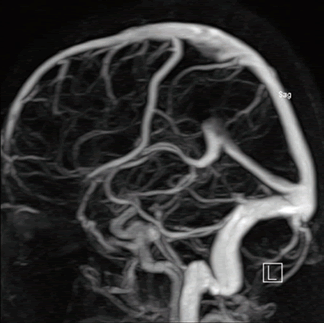

Диагностика магнитно-резонансная ангиография сосудов головного мозга производится при подозрении на тромбофлебит сигмовидного синуса.

- МРТ ангиографии сосудов головного мозга с контрастированием